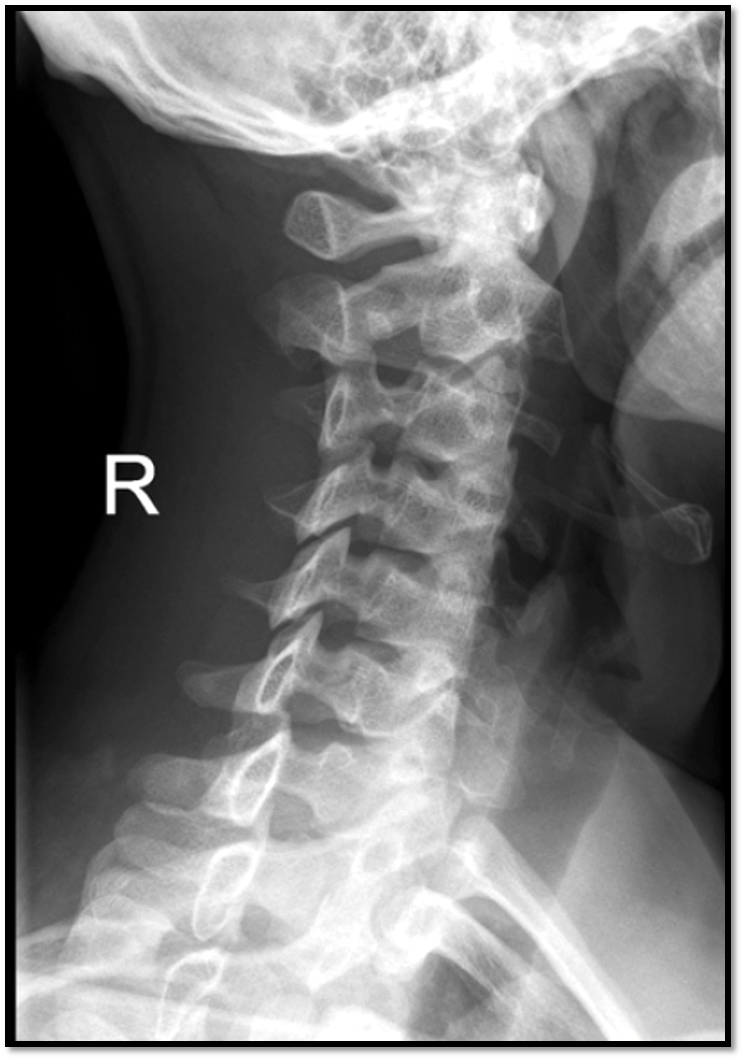

Q

What is the oblique and whats wrong with it

• RPO/LAO

• too steep of an oblique (pedicles too close to the middle)

• demonstrates left intervertebral foramina (they arent uniform)